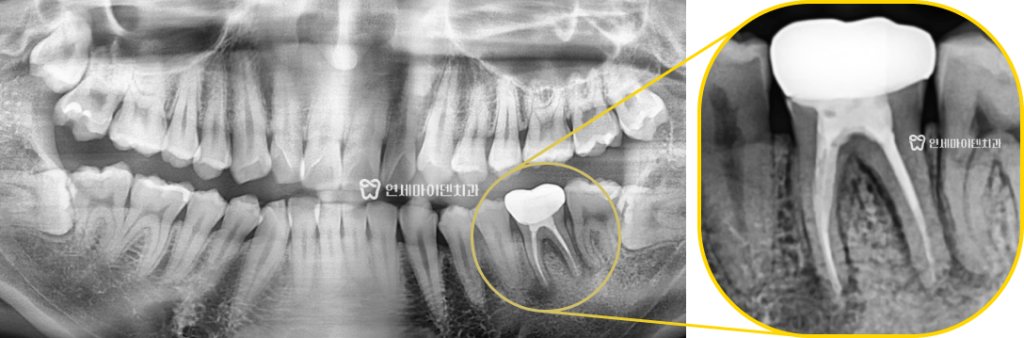

검사 결과, 문제의 치아는 아래 어금니 36번 치아였고

잇몸 근처에 검게 보이는 염증 소견이 있었습니다.

방사선 사진으로도 치근 끝 부위의 염증 반응이

분명히 보이는 것을 확인할 수 있습니다.

문제는 한쪽 뿌리의 염증 양상이 좋지 않았습니다.

염증의 위치나 모양이 치아에 금이 간 ‘크랙’때문에 생긴

염증의 양상과 유사해보였기 때문입니다.